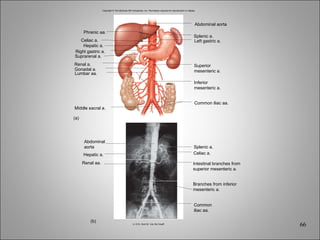

Copyright © The McGraw-Hill Companies, Inc. Permission required for reproduction or display. Hepatic a. Renal aa. Splenic a. Celiac a. (b) (a) Right gastric a. Hepatic a. Celiac a. Phrenic aa. Suprarenal a. Renal a. Middle sacral a. Gonadal a. Lumbar aa. Abdominal aorta Splenic a. Left gastric a. Common iliac aa. Superior mesenteric a. Inferior mesenteric a. Intestinal branches from superior mesenteric a. Branches from inferior mesenteric a. Common iliac aa. Abdominal aorta b: © Dr. Kent M. Van De Graaff

Copyright © TheMcGraw-Hill Companies, Inc. Permission required for reproduction or display. Hepatic a. Renal aa. Splenic a. Celiac a. (b) (a) Right gastric a. Hepatic a. Celiac a. Phrenic aa. Suprarenal a. Renal a. Middle sacral a. Gonadal a. Lumbar aa. Abdominal aorta Splenic a. Left gastric a. Common iliac aa. Superior mesenteric a. Inferior mesenteric a. Intestinal branches from superior mesenteric a. Branches from inferior mesenteric a. Common iliac aa. Abdominal aorta b: © Dr. Kent M. Van De Graaff